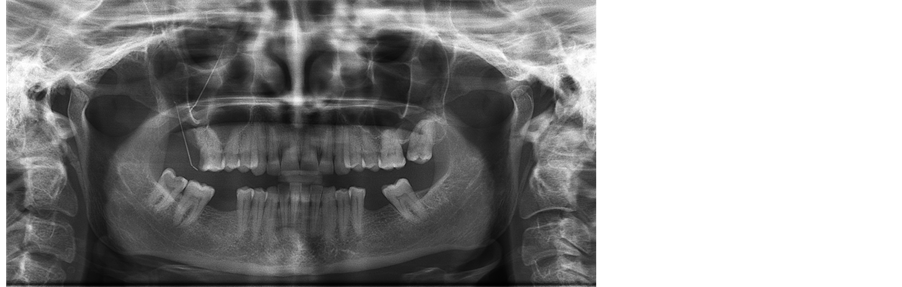

Periapical and panoramic radiograph confirmed the presence of GP point in the right maxillary sinus (Figure 1). Treatment was planned to retrieve the gutta percha point by Caldwell-Luc approach and closure of oroantral communication using buccal fat pad. The GP point were visualized and removed, the maxillary sinus irrigated and the wound was sutured with 3-0 vicryl.

Figure 1. Orthopantomogram showing foreign body (gutta percha point) in the right maxillary antrum.